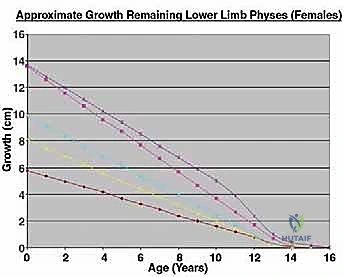

The core, absolute indication for an expandable prosthesis is the anticipated limb-length discrepancy at skeletal maturity. For the lower extremity, if the estimated leg-length discrepancy is calculated to be more than 3 cm, an expandable prosthesis is unequivocally indicated. Discrepancies exceeding 3 cm lead to severe pelvic obliquity, compensatory scoliosis, and significantly increased energy expenditure during ambulation. For projected discrepancies less than 3 cm, we might consider conventional "adult-type" prostheses, manufactured slightly longer (up to 1.5 cm) to over-lengthen the limb acutely, or we may opt for a contralateral epiphyseodesis to equalize limb lengths at maturity.

In the upper extremity, the functional tolerance for length discrepancy is significantly higher. The threshold for utilizing an expandable prosthesis in the arm is typically a projected discrepancy of more than 5 cm. If the discrepancy is less than 5 cm, we can frequently insert a conventional static prosthesis that is 2 to 3 cm longer than the resected segment, effectively allowing the contralateral, healthy limb to "catch up" during remaining growth. A slight arm-length discrepancy is predominantly a cosmetic concern, with true functional deficits in reach and bimanual activities arising only when the difference becomes massive.

Age, Chemotherapy, and Physeal Sacrifice

Bone tumors in children frequently occur in the metaphyseal region, directly adjacent to the most active growth plates (e.g., distal femur, proximal tibia). Achieving wide oncologic margins often necessitates the complete sacrifice of a major physis, leading to an immediate and profound growth arrest in that segment. Expandable prostheses are specifically designed to counteract this exact iatrogenic deficit. Furthermore, we must account for the systemic effects of neoadjuvant and adjuvant chemotherapy. Intensive cytotoxic regimens independently suppress global bone growth and delay skeletal maturation, further complicating LLD calculations and contributing to potential discrepancies.

Patient age and skeletal maturity are the final arbiters. Generally, females older than 11 years or males older than 13 years rarely require expandable prostheses. At these ages, the remaining growth potential of the affected physes usually translates to an estimated growth discrepancy of less than 3 cm. Utilizing an expandable implant in a patient nearing skeletal maturity exposes them to the mechanical risks of a complex device without the requisite benefit.

Beyond standard oncologic staging, we require specialized orthopaedic measurements. Measured full-length scanograms of both the affected and contralateral limbs are critical for calculating current limb length and templating the prosthesis. A standardized hand/wrist radiograph is obtained to estimate skeletal bone age using the Greulich and Pyle atlas. This provides a vastly more accurate prediction of remaining growth than chronological age alone. The Estimated Limb-Length Discrepancy (LLD) at skeletal maturity is then calculated. While traditionally derived using the Anderson and Green charts, the validated Multiplier Method has emerged as a highly accurate and simpler predictor, utilizing chronological age and a single length measurement to definitively determine if an expandable prosthesis is indicated.